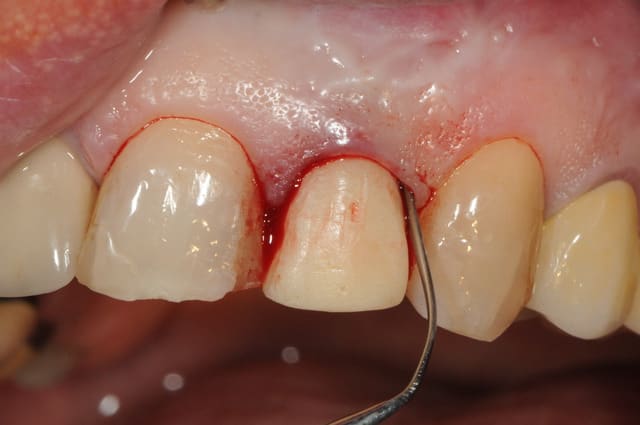

Le cas EII sur 12

positionnement de l'implant en ménageant un espace en vestibulaire qui st comblé avec de l'os synthétique car l'espace est important et il y a une perforation de la corticale vestibulaire en regard de l'apex de la dent.

pour recouvrir tout cela et gagner un peu de volume vestibulaire

un lambeau palatin pédiculé qui après une rotation va recouvrir l'implant et la greffe.